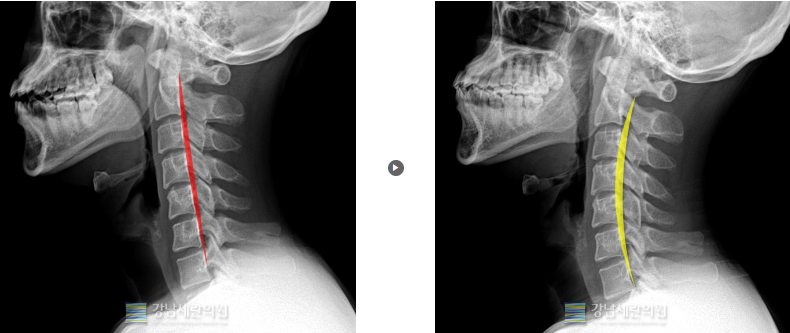

#일자목

일자목 교정 전 ▶ 일자목 30회(3개월) 치료 후

일자목 교정전 ▶ 일자목 30회(3개월) 치료 후